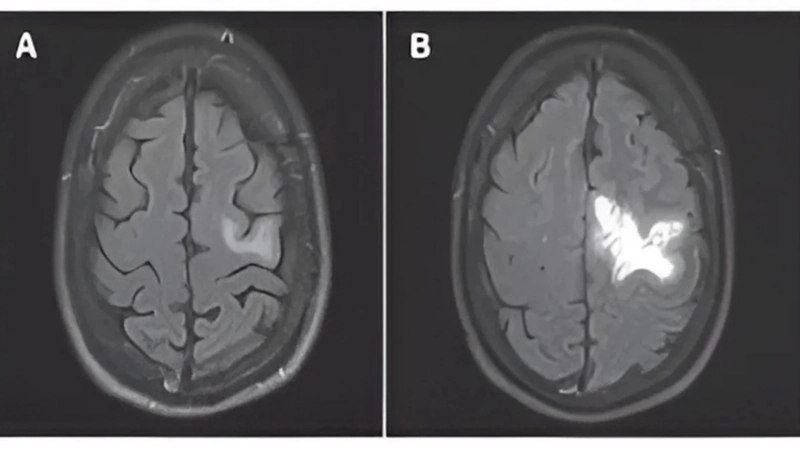

Natalizumab PML risk requires regular MRI monitoring